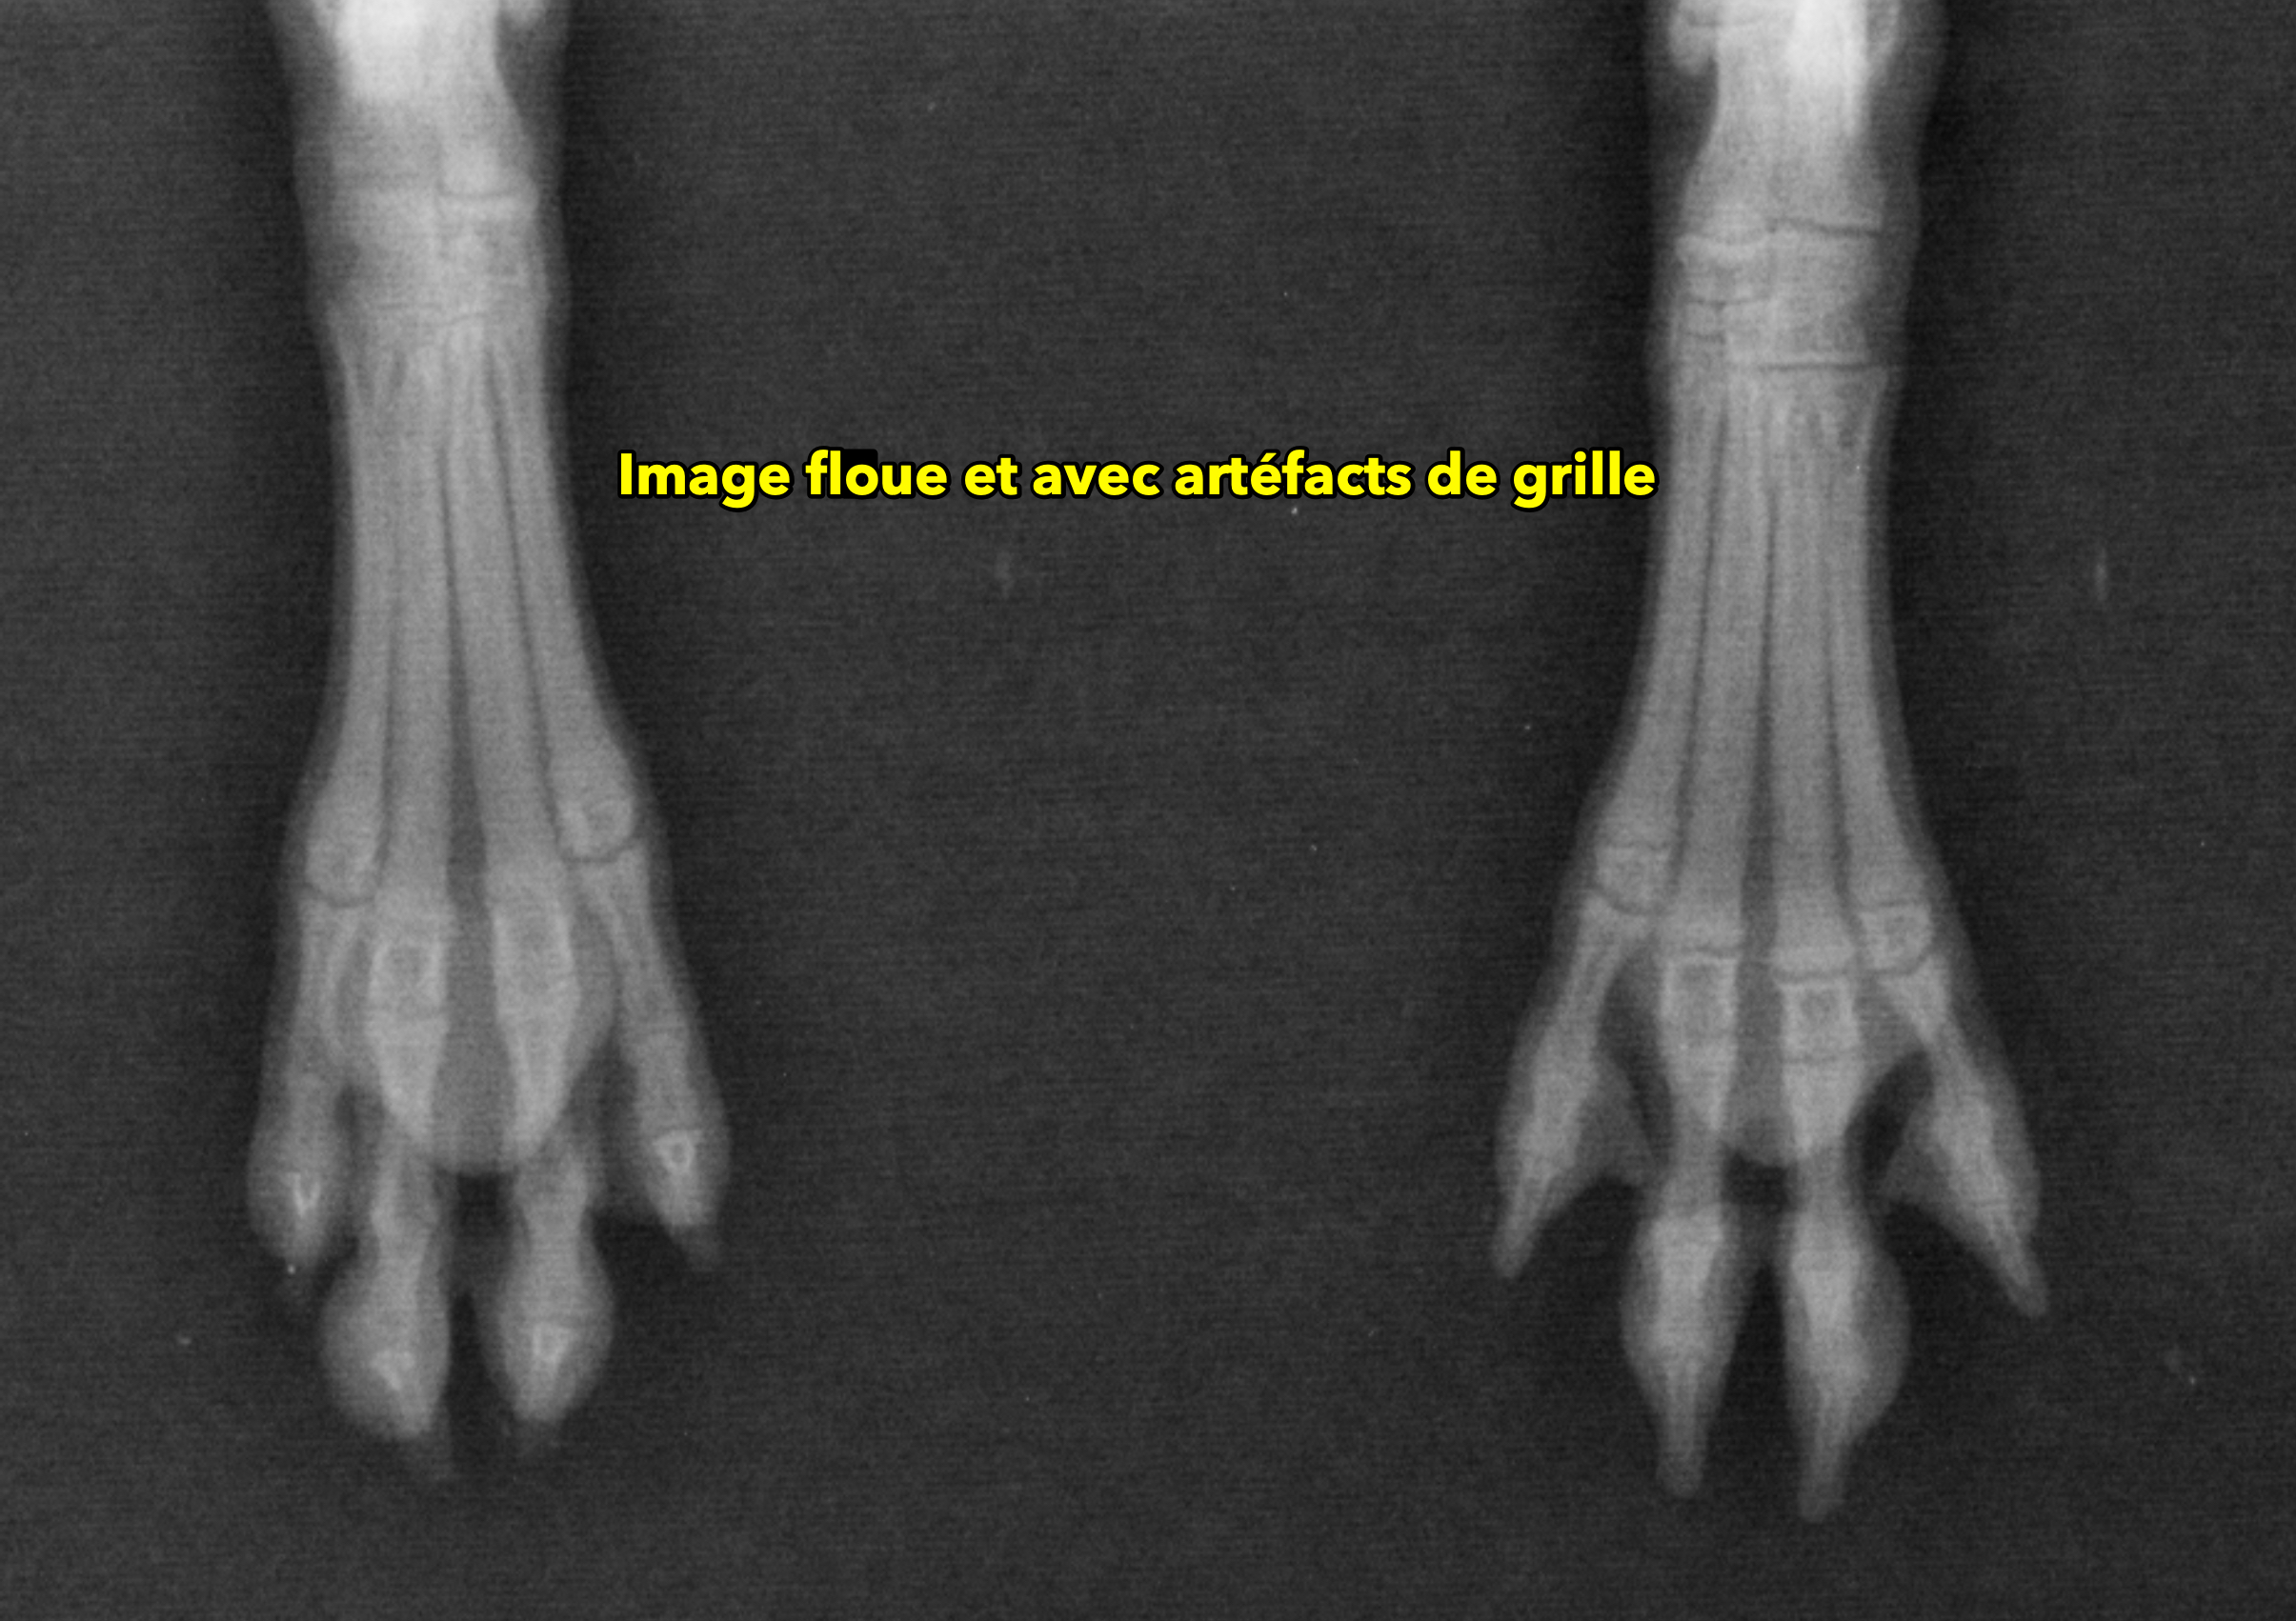

qualitecc81-8_radio-floue-et-artecc81facts